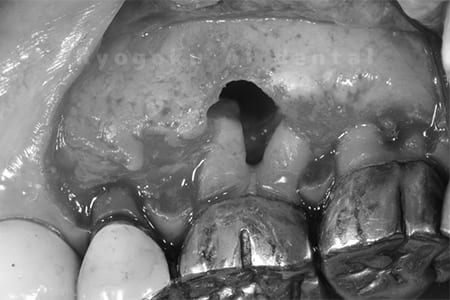

他院で根管治療を行ったが、なかなか治らず、抜歯を宣告されたとのことでご来院された患者様です。歯がかなり削られており、また、歯根の根尖部の病変が大きく、嚢胞化しているため、クラウンレングスニングと再植歯根端手術を同時に行いました。違和感もなくなり、大変満足されています。